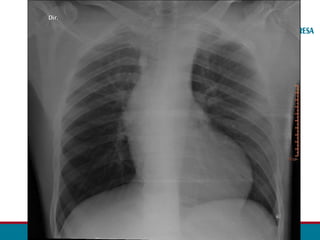

• F.A.F., sexo masculino, 16 anos.

• Ao realizar exames de rotina, o Eletrocardiograma evidenciou sinais

de sobrecarga do ventrículo esquerdo.

• Assintomático.

• Foram solicitados um ECOTT e uma ANGIOTC da Aorta.

ECG: Sinais de sobrecarga de ventrículo esquerdo

ANGIOTOMOGRAFIA DA AORTA TOTAL – 28/05: